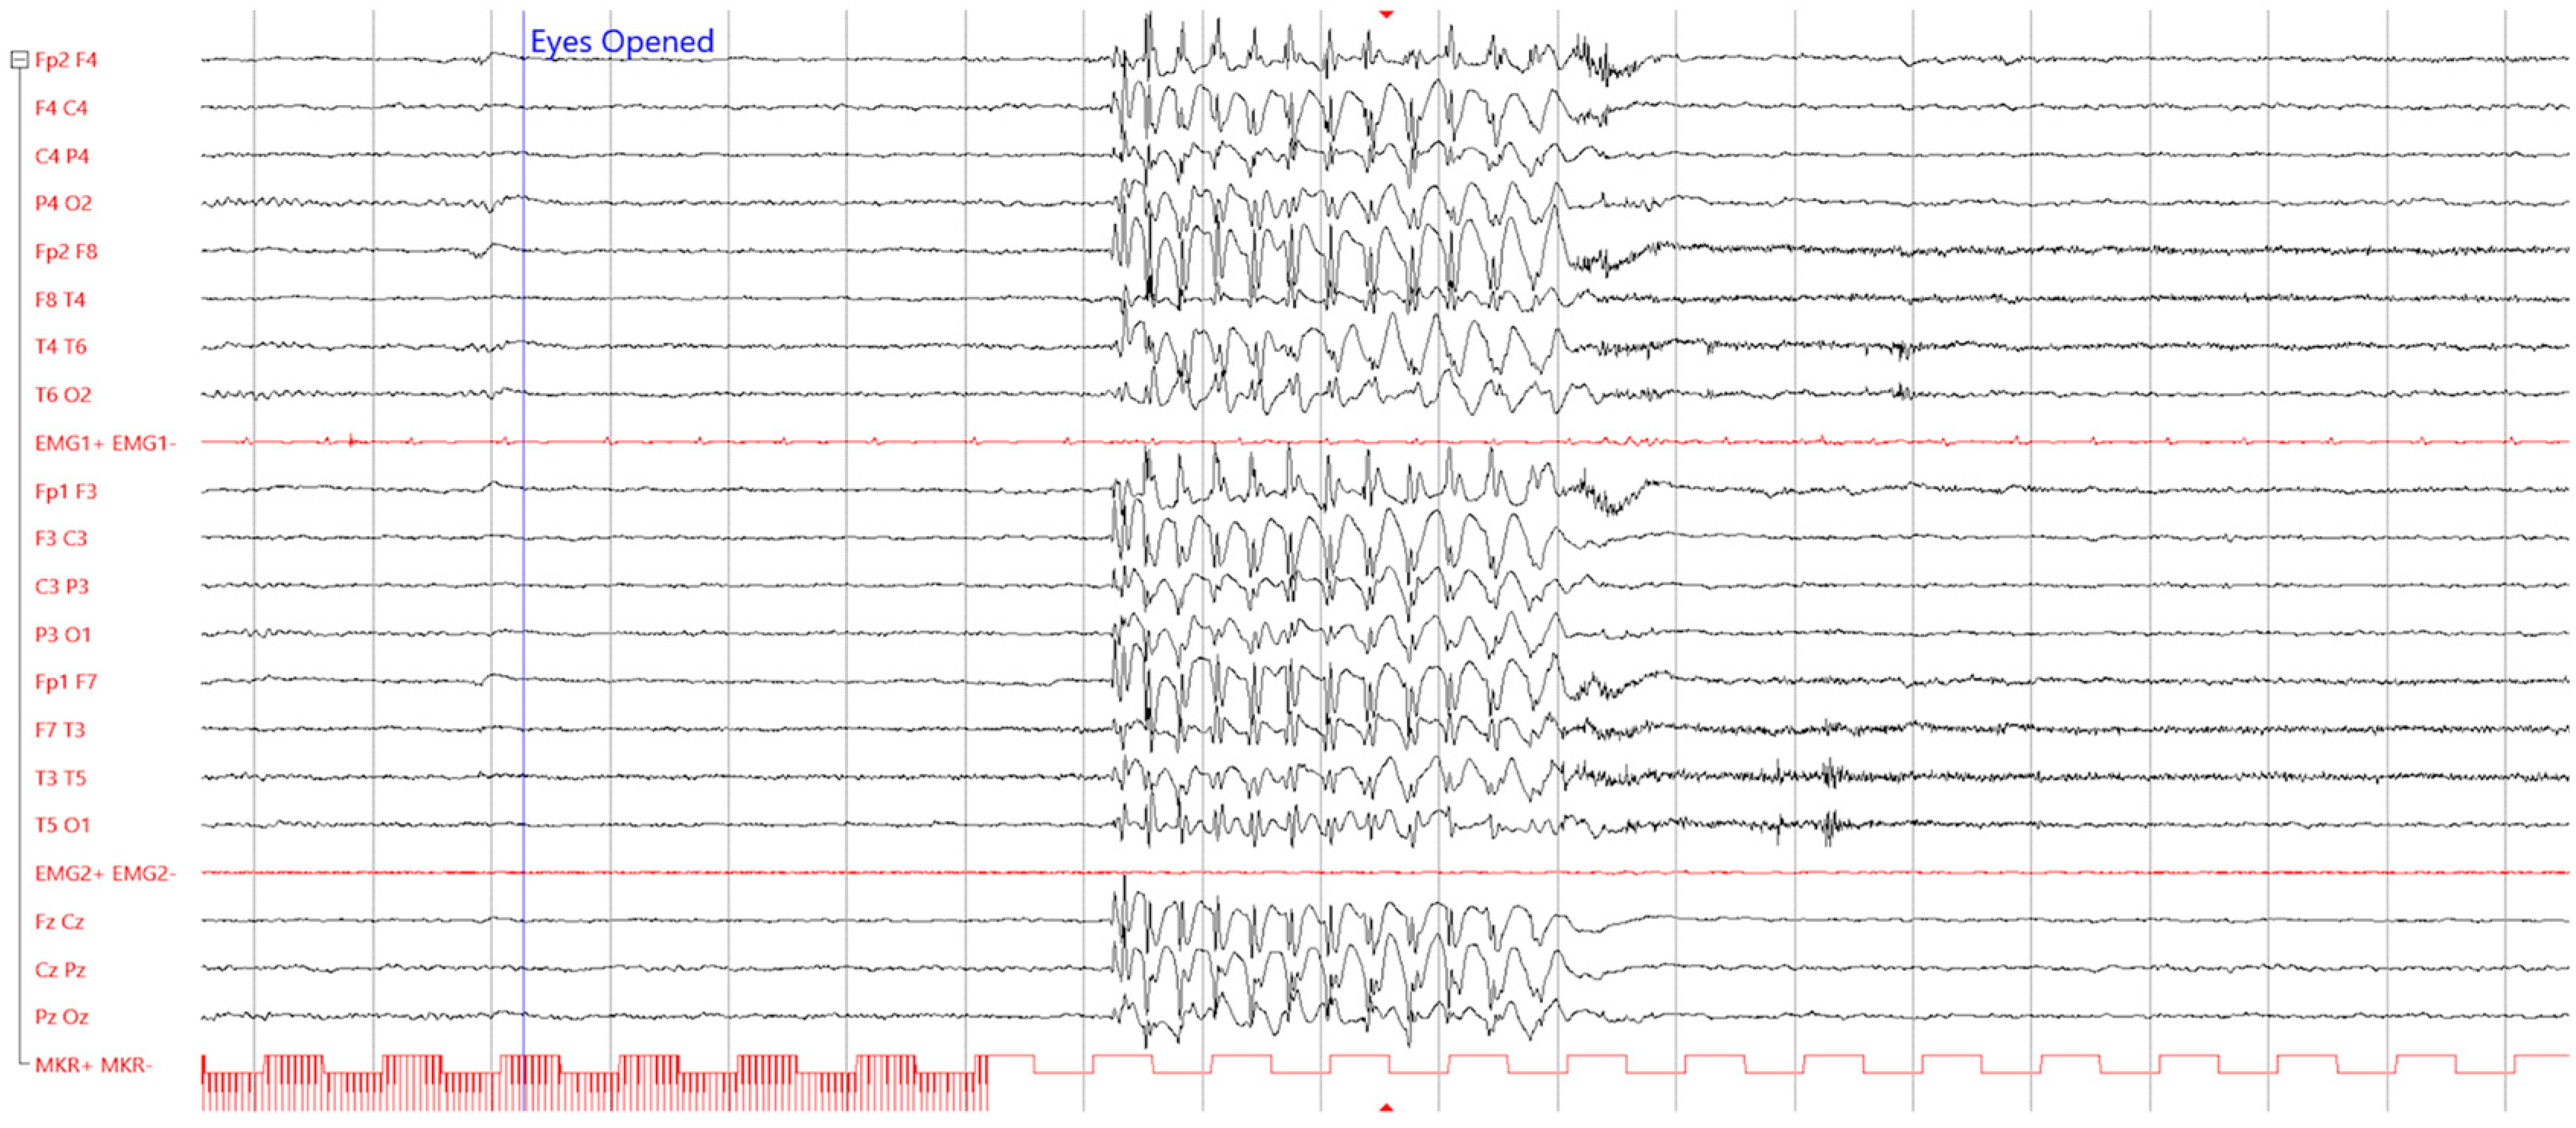

3.2.3. Diabetes Mellitus and Epilepsy Comorbidity

- Marcovecchio, M.L.; Petrosino, M.I.; Chiarelli, F. Diabetes and Epilepsy in Children and Adolescents. Curr. Diabetes Rep. 2015, 15, 21. [Google Scholar] [CrossRef] [PubMed]

- Verrotti, A.; Scaparrotta, A.; Olivieri, C.; Chiarelli, F. Seizures and type 1 diabetes mellitus: Current state of knowledge. Eur. J. Endocrinol. 2012, 167, 749–758. [Google Scholar] [CrossRef] [PubMed]

- Baglietto, M.G.; Mancardi, M.M.; Giannattasio, A.; Minuto, N.; Rossi, A.; Capovilla, G.; Veneselli, E.; Lorini, R.; D’Annunzio, G. Epilepsia partialis continua in type 1 diabetes: Evolution into epileptic encephalopathy with continuous spike-waves during slow sleep. Neurol. Sci. 2009, 30, 509–512. [Google Scholar] [CrossRef]

- McCorry, D.; Nicolson, A.; Smith, D.; Marson, A.; Feltbower, R.G.; Chadwick, D.W. An association between type 1 diabetes and idiopathic generalized epilepsy. Ann. Neurol. 2005, 59, 204–206. [Google Scholar] [CrossRef]

- Caietta, E.; Halbert, C.; Lépine, A.; Khammar, A.; Cano, A.; Gavaret, M.; Mancini, J.; Villeneuve, N.; Chabrol, B.; Simonin, G.; et al. Association of type 1 diabetes mellitus and epilepsy in children. A cohort of 10 cases. Arch. Pediatr. 2012, 19, 9–16. [Google Scholar] [CrossRef]

- Graus, F.; Saiz, A.; Dalmau, J. GAD antibodies in neurological disorders—Insights and challenges. Nat. Rev. Neurol. 2020, 16, 353–365. [Google Scholar] [CrossRef]

- Ganelin-Cohen, E.; Modan-Moses, D.; Hemi, R.; Kanety, H.; Ben-Zeev, B.; Hampe, C.S. Epilepsy and behavioral changes, type 1 diabetes mellitus and a high titer of glutamic acid decarboxylase antibodies. Pediatr. Diabetes 2016, 17, 617–622. [Google Scholar] [CrossRef]

- Aguiar, T.S.; Dantas, J.R.; Cabral, D.B.; Rêgo, C.C.S.; Zajdenverg, L.; Salles, G.F.; Alves-Leon, S.V.; Rodacki, M.; Lima, M.A. Association between high titers of glutamic acid decarboxylase antibody and epilepsy in patients with type 1 diabetes mellitus: A cross-sectional study. Seizure 2019, 71, 318–321. [Google Scholar] [CrossRef] [PubMed]